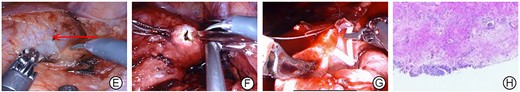

After communicating with the patient, we performed a RALP. The surgery used a transabdominal approach, and an ectopic kidney was seen on the right side of the lower abdomen with a markedly dilated hydronephrosis. A fibrous strip was removed from the pelvic ureteral junction, and a 5 Fr double ‘J’ catheter was put directly into the ureter (Fig. 2E–G). The operation took 175 min. Postoperative pathological findings are irregular proliferation of surrounding fibrous and smooth muscle tissue (Fig. 2H). The patient’s pain disappeared after surgery. No complications occurred such as urinary leakage or urinary tract infection during the perioperative period. The patient was discharged from hospital 3 days after the surgery. Double ‘J’ catheter was removed 6 weeks after surgery. The blood of urea nitrogen was 4.30 mmol/L, the serum creatinine was 92 μmol/L and the GFR was 101.350 ml/min 3 months after the surgery. CT showed significant reduction in hydronephrosis (Fig. 3I and J).

Intraoperative images and postoperative pathology of the patient. (E) Significant hydronephrosis with dilated renal pelvis (the red arrow); (F) the dilated renal pelvis is incised;(G) sutured renal pelvis after the placement of double J ureteral catheter; (H) pathology is an irregular proliferation of surrounding fibrous and smooth muscle tissue.